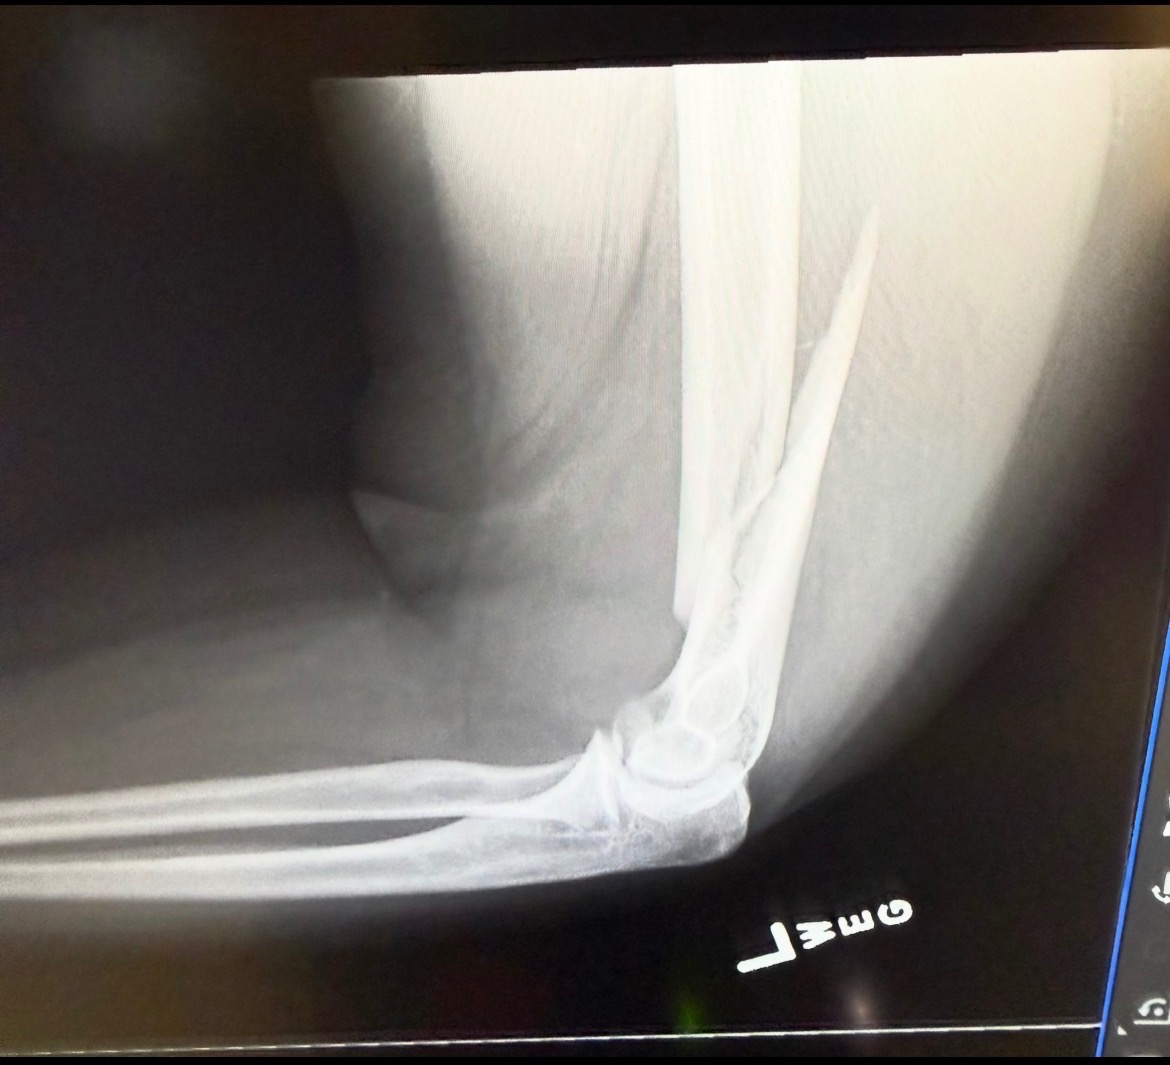

I now sport a broken arm due to a slip and trip on some stairs. I tried to catch myself on the railing, instead, my arm got caught but my body kept falling. After a trip to the ER for some X-rays, they gave me the news, broken humerus right above the elbow.